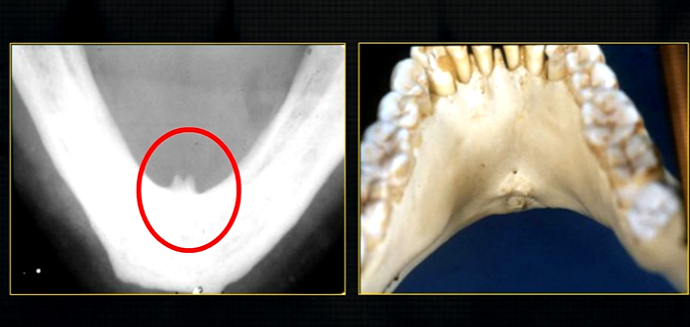

dense, white, radiopaque line → dense bone of mylohyoid ridge

underneath mylohyoid ridge - looks more radiolucent → this is due to the lingual indentation of submandibular fossa

dense cortical bone of the lower border

radiolucent shadow created by the lingual pit